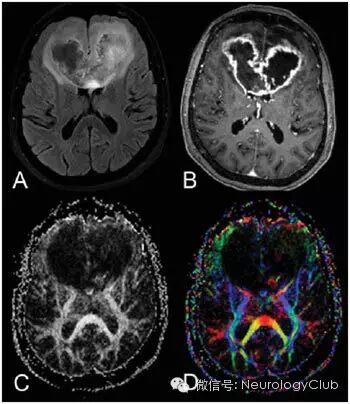

CT显示肿瘤呈边界不清的混杂密度影,常见瘤内出血所致高密度或囊性变、坏死;肿瘤跨胼胝体生长至对侧大脑半球时,呈“蝴蝶征”,水肿和占位效应明显。MRI在一定程度上能够揭示肿瘤的病理改变:T1WI呈不均匀低信号(图 1a),多合并坏死、囊性变或出血性改变;T2WI呈混杂高信号,中心坏死区为高信号,肿瘤生长区周围呈等信号,部分病变与肿瘤周围水肿分界不清,肿瘤内异常血管增生形成线样“流空效应”区(图 1b)。增强扫描肿瘤边缘呈显著对比强化,呈“花环”(ring/rim-enhancing)样(图 1c)、不规则环形、岛形或螺旋形改变;囊变性和坏死区周围肿瘤实质呈特征性“假栅栏征”,即圆形、椭圆形未强化区散在分布在强化区内,类似乳突蜂窝小房。DWI多呈高信号,ADC值明显减低。MRS提示NAA峰降低,Cho升高明显,MI峰较低级别星形细胞瘤低。灌注成像显示,病灶周围和病灶内有多处高灌注区(图 1d),提示大量肿瘤血管生成。胶质母细胞瘤虽具典型影像学特征,但仍需注意与颅内单发转移瘤、间变性胶质瘤、淋巴瘤等肿瘤性病变,以及脑脓肿、结核瘤、脱髓鞘假瘤等非肿瘤性占位性病变相鉴别。

(图7:MRI增强肿瘤呈混杂信号)

(图8:胶质母细胞瘤周围水肿)